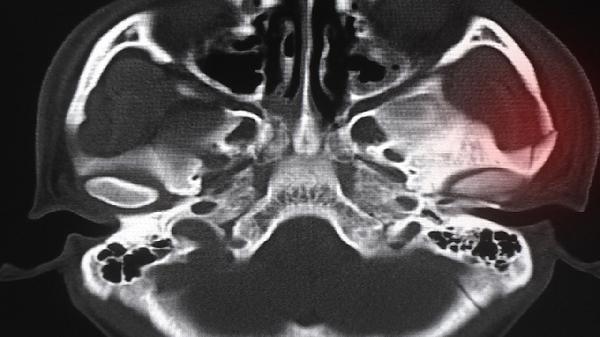

鼻骨双侧远端局部不连续是什么意思

鼻骨双侧远端局部不连续通常指影像学检查发现鼻骨远端存在断裂或裂隙,可能由外伤、发育异常或病理因素导致。需结合临床症状判断严重程度,常见原因有鼻部外伤、先天性鼻骨发育不良、鼻部肿瘤压迫等。

鼻部外伤是导致鼻骨双侧远端局部不连续的最常见原因。外力撞击可能导致鼻骨远端出现线性骨折或粉碎性骨折,多伴有鼻部肿胀、疼痛、皮下淤血等症状。轻微骨折可通过手法复位配合外固定治疗,严重骨折需手术复位。先天性鼻骨发育不良表现为鼻骨远端自然裂隙,通常无须特殊处理,但可能影响鼻腔通气功能。鼻部肿瘤生长过程中可能压迫鼻骨导致骨质吸收,出现局部不连续表现,需通过病理检查明确肿瘤性质。

影像学检查发现鼻骨双侧远端局部不连续时,需结合患者病史和临床表现综合判断。外伤性骨折往往有明确外伤史和急性症状,发育异常多无不适症状,病理性改变可能伴随鼻塞、出血等异常表现。建议尽早就医明确诊断,避免延误治疗时机。医生会根据具体情况选择鼻内镜检查、CT三维重建等进一步检查手段。